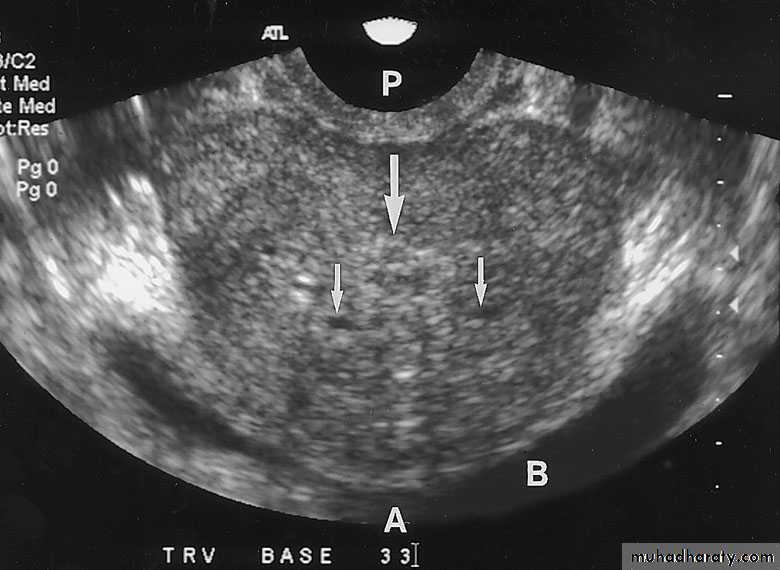

TRUS (transrectal U/S): for prostate evaluation and U/S guided prostate biopsy.

Color-flow Doppler techniques - measuring blood flow